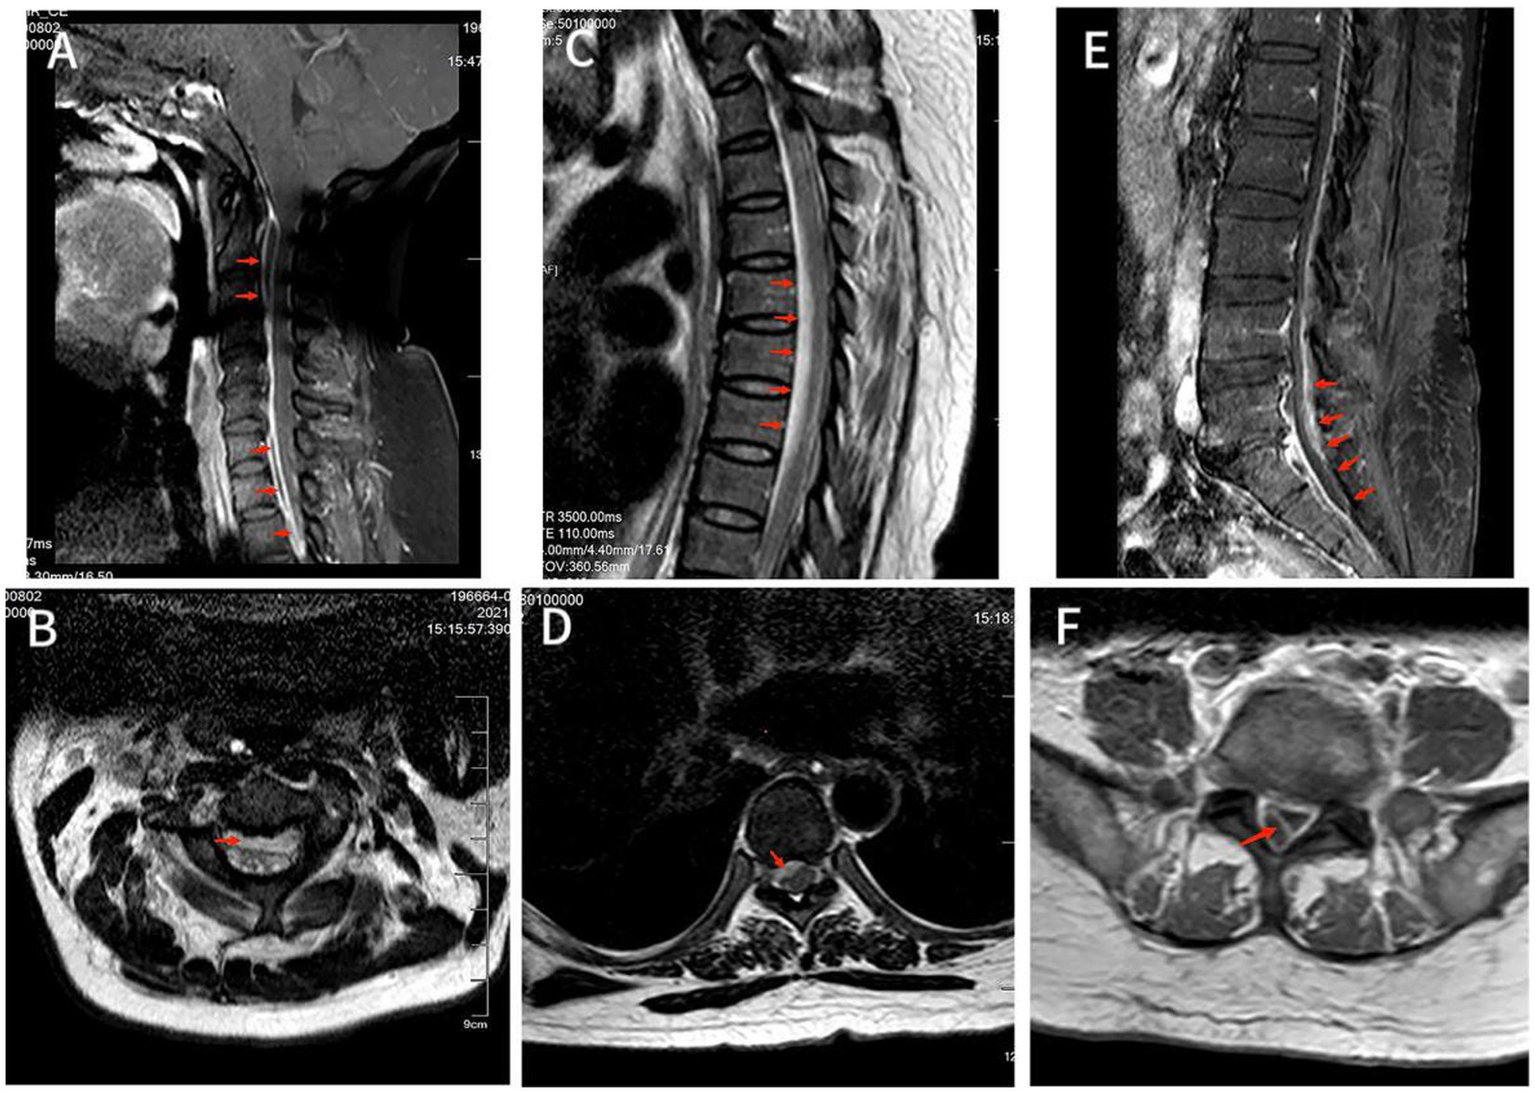

Figure 1

(A) MRI T2-weighted image showed hyperintensity of the lesion on the ventral side of the spinal cord in the C2-C6 spinal canal. Also saw C5/6 intervertebral disc herniation and the corresponding dura and spinal cord were compressed. (B) Axial T2-weighted image showed an annular high signal lesion in the anterior part of the spinal cord within the spinal canal of C2, and spinal cord compression at the C2. (C) T2-weighted image showed hyperintensity of lesions ventral to the spinal cord in the T2-T8 spinal canal, with corresponding levels of spinal cord compression degeneration. (D) Axial T2-weighted image showed annular high signal lesion in the right anterior part of the spinal cord within the spinal canal of T7 accompanied by nerve root and spinal cord compression. (E) T1-enhanced image showed disc bulging in L3/4, L4/5 and L5/S1 with annular enhancement of the lesion ventral to the spinal cord in the L4-S1 spinal canal with spinal cord compression at the corresponding level, but no significant internal enhancement. (F) Axial T1-enhanced image showed a large range of irregular non-enhanced areas in the soft tissue of the right posterior side of the at the L5 level, and a ring-enhancing lesion in the right posterior part of the intradural sac with no obvious internal enhancement.